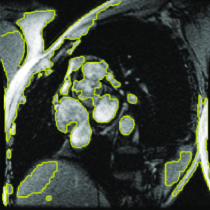

Appearance is one of the most important visual cues to distinguish between different structures in an image. Appearance is described by studying the distribution of different features such as intensity values in gray-scale images, color, and texture inside each object. In most cases, appearance models are incorporated into the data term in (2) and (7). The purpose of incorporating appearance prior is to fit the appearance distribution of the segmented objects to the distribution of objects of interest, e.g. using Gaussian mixture model (GMM) (Rother et al., 2004). In the literature, there are two ways to model the appearance: 1) adaptively learning the appearance during the segmentation procedure, and 2) knowing the appearance model prior to performing segmentation (e.g. by observing the appearance distribution of the training data). In the former case, the appearance model is learned as the segmentation is performed (Vese and Chan, 2002) (computed online). In the second case, it is assumed that the probability of each pixel belonging to particular label is known, i.e. if represents a particular set of feature values (e.g. intensity/color) associated with each image location for object, then it is assumed that is known (or pre-computed offline). This probability is usually learned and estimated from the distribution of features inside small samples of each object. Figure 9 illustrates the probability of different structures (the kidney, the tumour, and the background) in an endoscopic scene. A lower intensity in Figures 9(b-d) corresponds to higher probability.